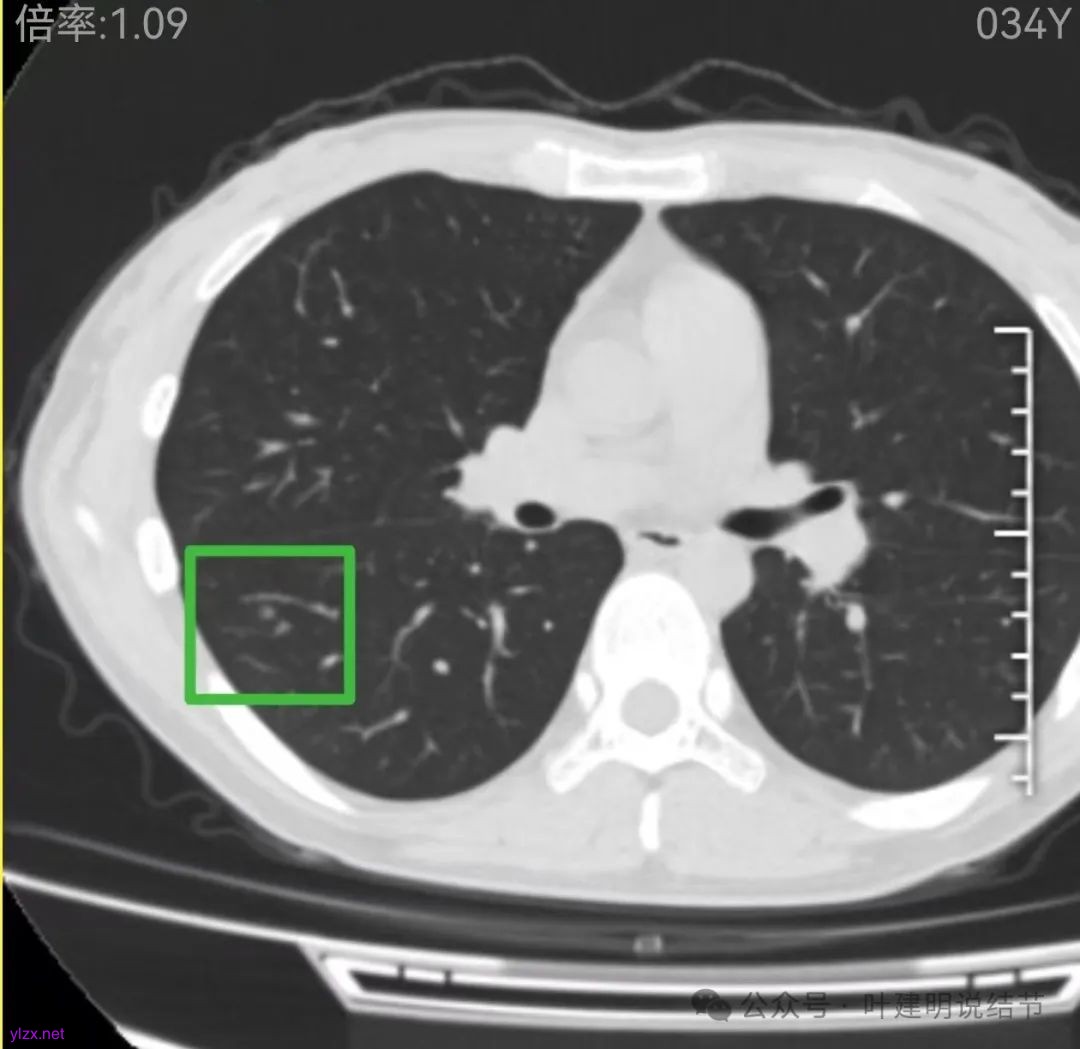

右下当时是很淡的,也显偏模糊的磨玻璃影。

怎么有个点状密度较高的结节在?与上面那截图的淡磨并不完全在一块的。

密度甚高,边界与轮廓清楚,只看这真的不像恶性些。

边缘区也瘤肺界限稍糊,整体轮廓还行。有进展的是不是就是淡磨那处?